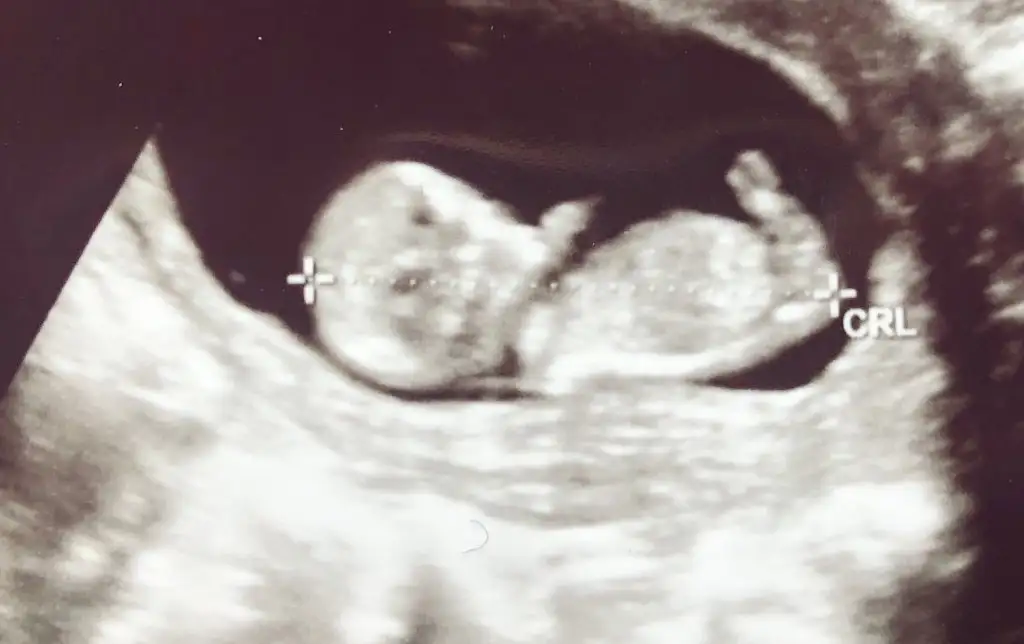

Kızlar yorumlayabilirmisniz size zahmet 10 haftalık

Eklentiler

• IMG_20200101_185610.webp

33,3 KB · Görüntüleme: 66